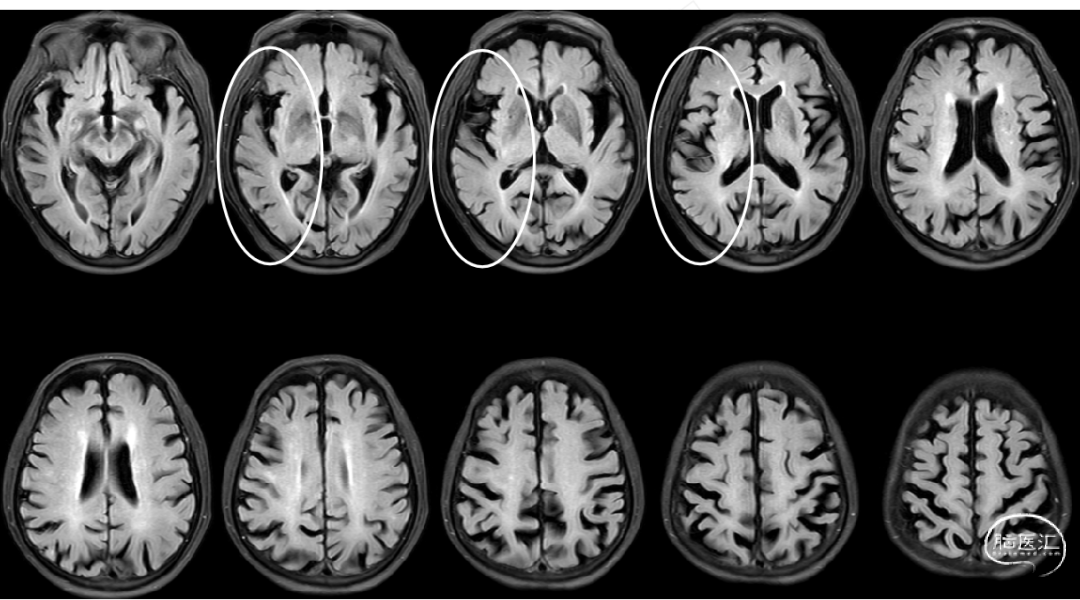

术前影像检查

MRA:右侧大脑中动脉闭塞。

DWI:右侧额顶叶、岛叶、基底节区新鲜梗死病灶。

Cranial DWI:右侧壳核、侧脑室旁小片状+皮层点状弥散受限。

Cranial SWI:SVS+AHVs RMCA M1长条血栓。

T2 Flair:丰富的高信号血管征(HVS)。

RICA C1闭塞,来自RACA丰富的软膜支代偿。